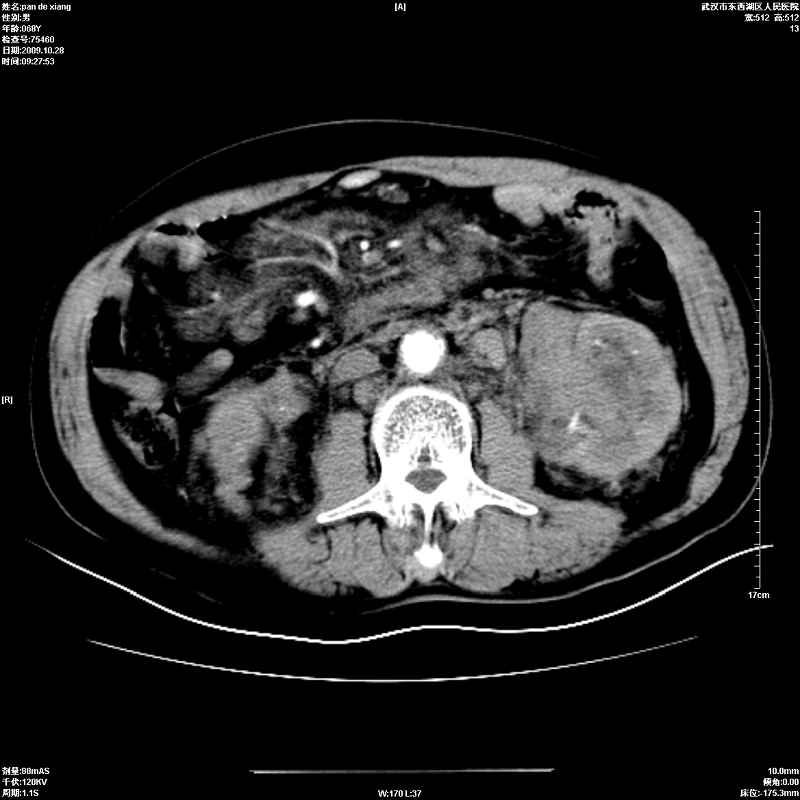

以下是引用杀毒软件在2009-10-28 20:41:00的发言:[br]结合临床考虑---白血病双肾改变或淋巴瘤。

以下是引用zxl51642在2009-10-29 9:59:00的发言:[br]结合临床“单克隆免疫球蛋白血症”,考虑双肾为继发损害并肾功能不全(尿中大量igg及少量iga、igm等大分子免疫球蛋白滤出所致继发损害),椎前软组织肿块为髓外造血。与浆细胞瘤有区别,平扫时有战友说的很清楚。